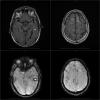

Varón de 46 años en el día 21 de postoperatorio de trasplante cardiaco, en  tratamiento inmunosupresor con tacrolimus, micofenolato de mofetilo y prednisona. Presenta un primer episodio de crisis tónico clónica generalizada que cede con...

Neurología: OtrosEtiología: Tóxica-yatrogeniaDiagnóstico final: Sindrome de encefalopatia posterior reversibleNivel de certeza: